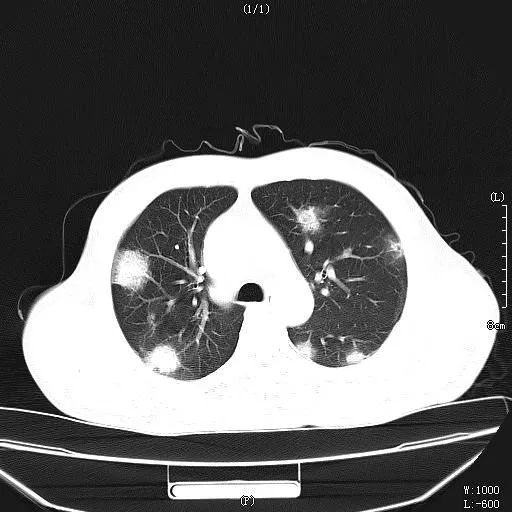

但该患者,再次不遵守医嘱,2018年6月开始再次停用抗病毒药物,9月出现高度黄疸,恶心,呕吐等症状,肝功能急剧恶化,入院第3天出现肝昏迷,经过“人工肝”等治疗,病情一度好转,神志转清,但最终出现肺部“毛霉菌”感染,高热到40℃,最终多脏器衰竭死亡。

肺部感染病灶